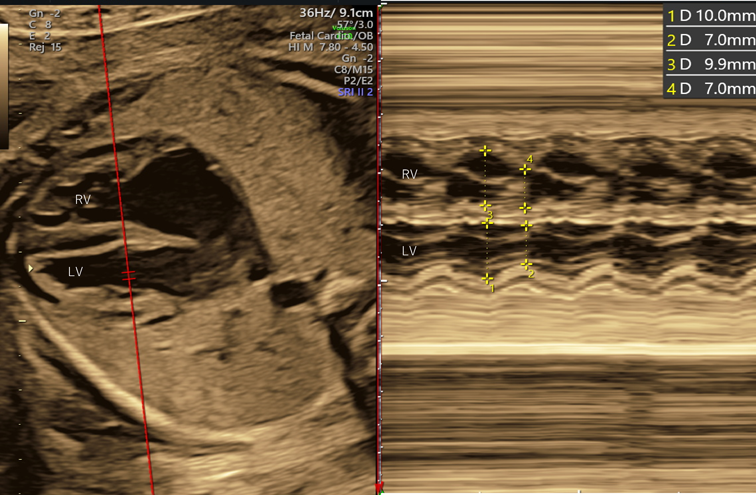

5. 心室内径短縮率(fractional shortening; FS)

収縮能の指標として用いられる.各心室のFSはMモード法を用いて計測した拡張期と収縮期の心室径から計算する.四腔断面で,カーソルを心室中隔に対してほぼ垂直になるように房室弁直下に設定し,各心室の拡張末期径と収縮末期径を計測する(Fig. 5).拡張末期径と収縮末期径の差を拡張末期径で除することで算出される.右心室・左心室ともに正常値は週数によらず一定で0.28~0.40前後とされる16).ただしカーソルの位置や角度などが少し変わると値が大きく変動してしまう16).真のFS低下は心不全がかなり進行した状態である. FS 拡張末期内径-収縮末期内径 拡張末期内径

Pediatric Cardiology and Cardiac Surgery 40(4): 250-259 (2024)

Fig. 5 心室内径短縮率(FS)

正常胎児におけるFSの計測.左室(LV)FS=(10.0–7.0)/10.0=0.30.右室(RV)FS=(9.9–7.0)/9.9=0.29.FS, fractional shortening.